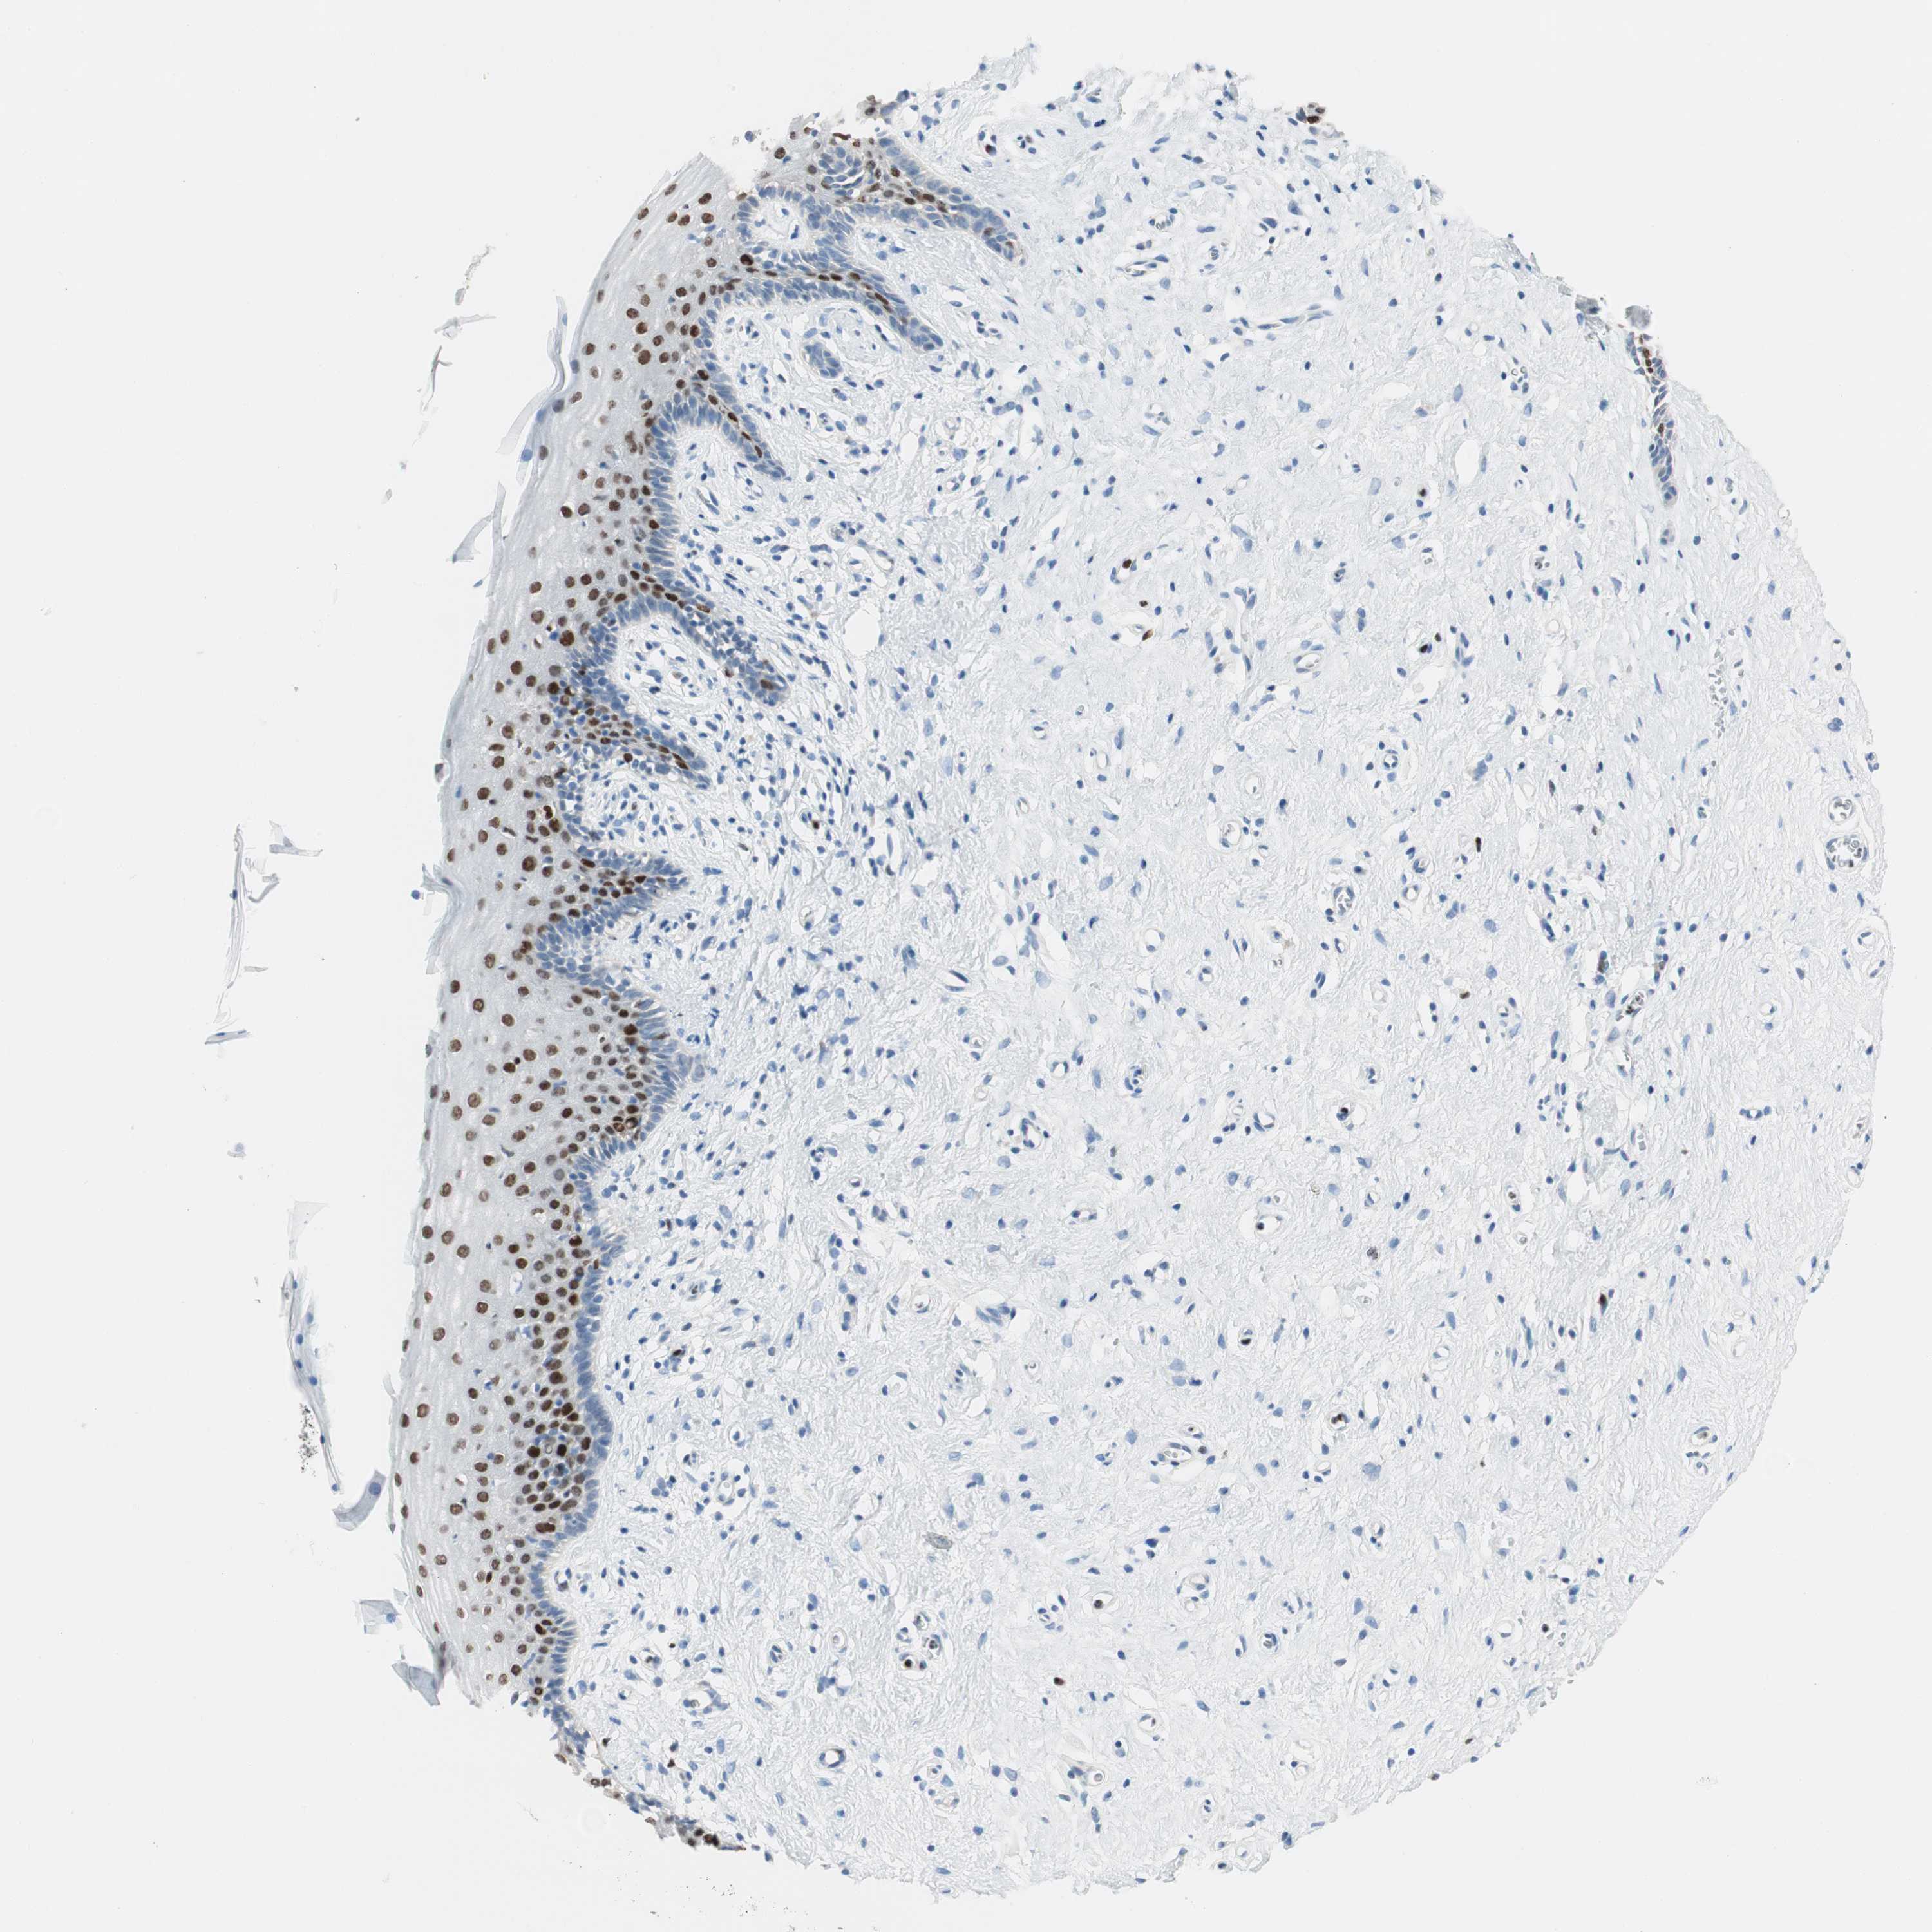

VAGINA - Antibody stainingi

Antibody staining in the annotated cell types in the current human tissue is reported as not detected, low, medium, or high, based on conventional immunohistochemistry profiling in selected tissues. This score is based on the combination of the staining intensity and fraction of stained cells.

Each image is clickable and will lead to virtual microscopy that enables deeper exploration of all samples and also displays staining intensity scores, fraction scores and subcellular localization as well as patient and tissue information for each sample.

Antibody CAB009589

Squamous epithelial cells High